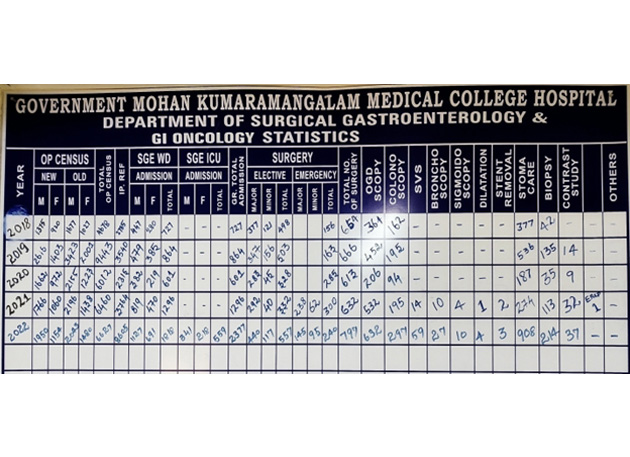

Census:

During the COVID years 2020 and 2021, the performance of our SGE Department was highest in entire state of Tamilnadu under the CMCHIS scheme. Also, we have always been one among the Top two highest performing SGE departments in the entire state under the CMCHIS scheme.

| S. No. | Year | Total OP Census | Total Ward Census | Elective Surgeries | Emergency Surgeries | OGD Scopy | Colono Scopy | SVS | Broncho Scopy | Sigmoid Scopy |

|---|---|---|---|---|---|---|---|---|---|---|

| 1. | 2018 | 4678 | 727 | 498 | 156 | 364 | 162 | |||

| 2. | 2019 | 9443 | 864 | 503 | 163 | 452 | 195 | |||

| 3. | 2020 | 6012 | 601 | 328 | 285 | 206 | 94 | |||

| 4. | 2021 | 6460 | 1296 | 332 | 300 | 532 | 195 | 14 | 10 | 4 |

| 5. | 2022 | 5690 | 1925 | 449 | 210 | 526 | 239 | 47 | 21 | 4 |

| 6. | 2023 (Until July) | 3121 | 1142 | 293 | 195 | 457 | 195 | 21 | 19 | 13 |